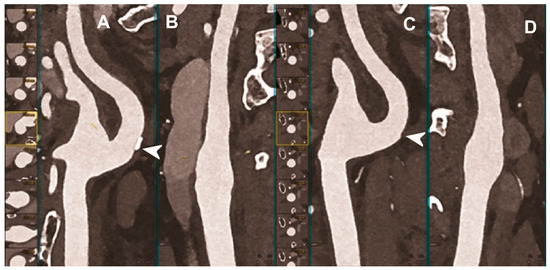

5.1. Coronary Imaging

CCTA is the favored imaging modality for the non-invasive assessment of coronary artery disease (CAD), allowing us to visualize the coronary lumen, assess stenosis, and identify plaque features in three dimensions [70] (Figure 2). In this context, the high or ultra-high spatial resolution, achievable with both UHR EID-CT or PCCT scanners, could be particularly beneficial. Indeed, it conveys the potential for a more comprehensive evaluation of the coronary tree, a more precise grading of stenosis, and a better evaluation of segments with stents or extensive calcifications [71].

Figure 2.

Cardiac CT using photon-counting computed tomography. The figure shows advanced multiplanar reconstructions of a coronary tree derived from a Photon-Counting CT (Scanner: NAEOTOM Alpha, Siemens) acquisition (A–C). In (A) we can see the right coronary artery with 2 stents (arrowheads), one proximal and one distal (much smaller), without any issue in the intrastent visualization of the arterial lumen. In (B), the left anterior descending coronary artery is depicted along its entire course (down to and beyond the left ventricular apex) with great detail and an evident deep intramyocardial course in the middle segment of the vessel (arrowhead). In (C), the left circumflex coronary artery also shows a stent with perfect intrastent visualization and patency (arrowhead).

The largest published clinical study of PCCT for CAD, involving 92 patients, demonstrated excellent imaging quality, a very high CNR, and a good ability to assess coronary segments and vessels, even in cases of calcified plaques and stents [72]. Indeed, only 5% of the segments were rated non-diagnostic. The radiation dose was generally low and depended strongly on the scan mode. Nine patients also underwent invasive coronary angiography as reference standard and the PCCT showed very high diagnostic performance for significant CAD on a per segment level (sensitivity 92% and specificity 96%).